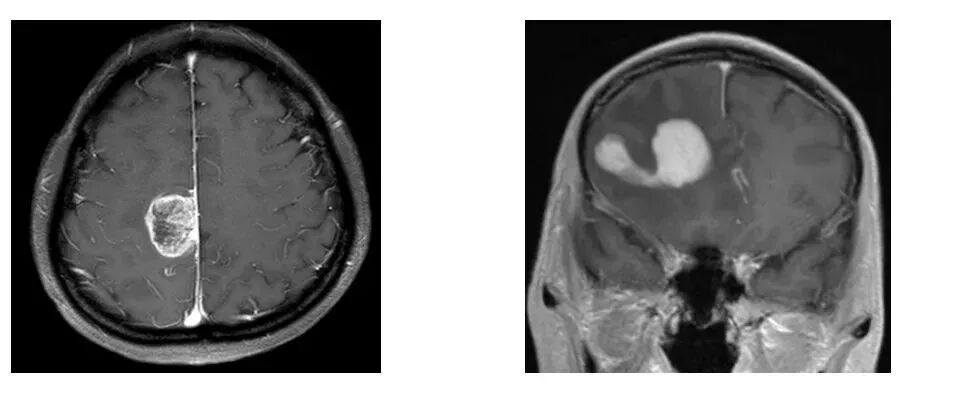

先看病例!下图哪个是胶质母细胞瘤,哪个是淋巴瘤吗?

怎么买病理图文这些影像征象背后的病理基础,今天才知道!_https://www.jmylbn.com_新闻资讯_第2张

应该难不住大家。明显坏死、毛线磨玻璃样强化的是胶质母细胞瘤(左),均匀强化、有脐凹征的是淋巴瘤(右)。

胶质母细胞瘤:WHO IV的高度恶性弥漫性胶质瘤,组织学上有细胞密集,有奇形核,巨形核,核分裂象,有典型的微血管增生和假栅栏样坏死,IDH野生型(IDH突变型有以上特点的,归于星形细胞瘤 CNS WHO IV,不再用胶质母细胞瘤 IDH突变型这一称呼);或者组织学上属于WHO II级或III级的IDH野生型弥漫性性形细胞瘤,伴EGFTR扩增、第7号染色体扩增/第10号染色体缺失、TERT启动子突变以上3种变异之一。